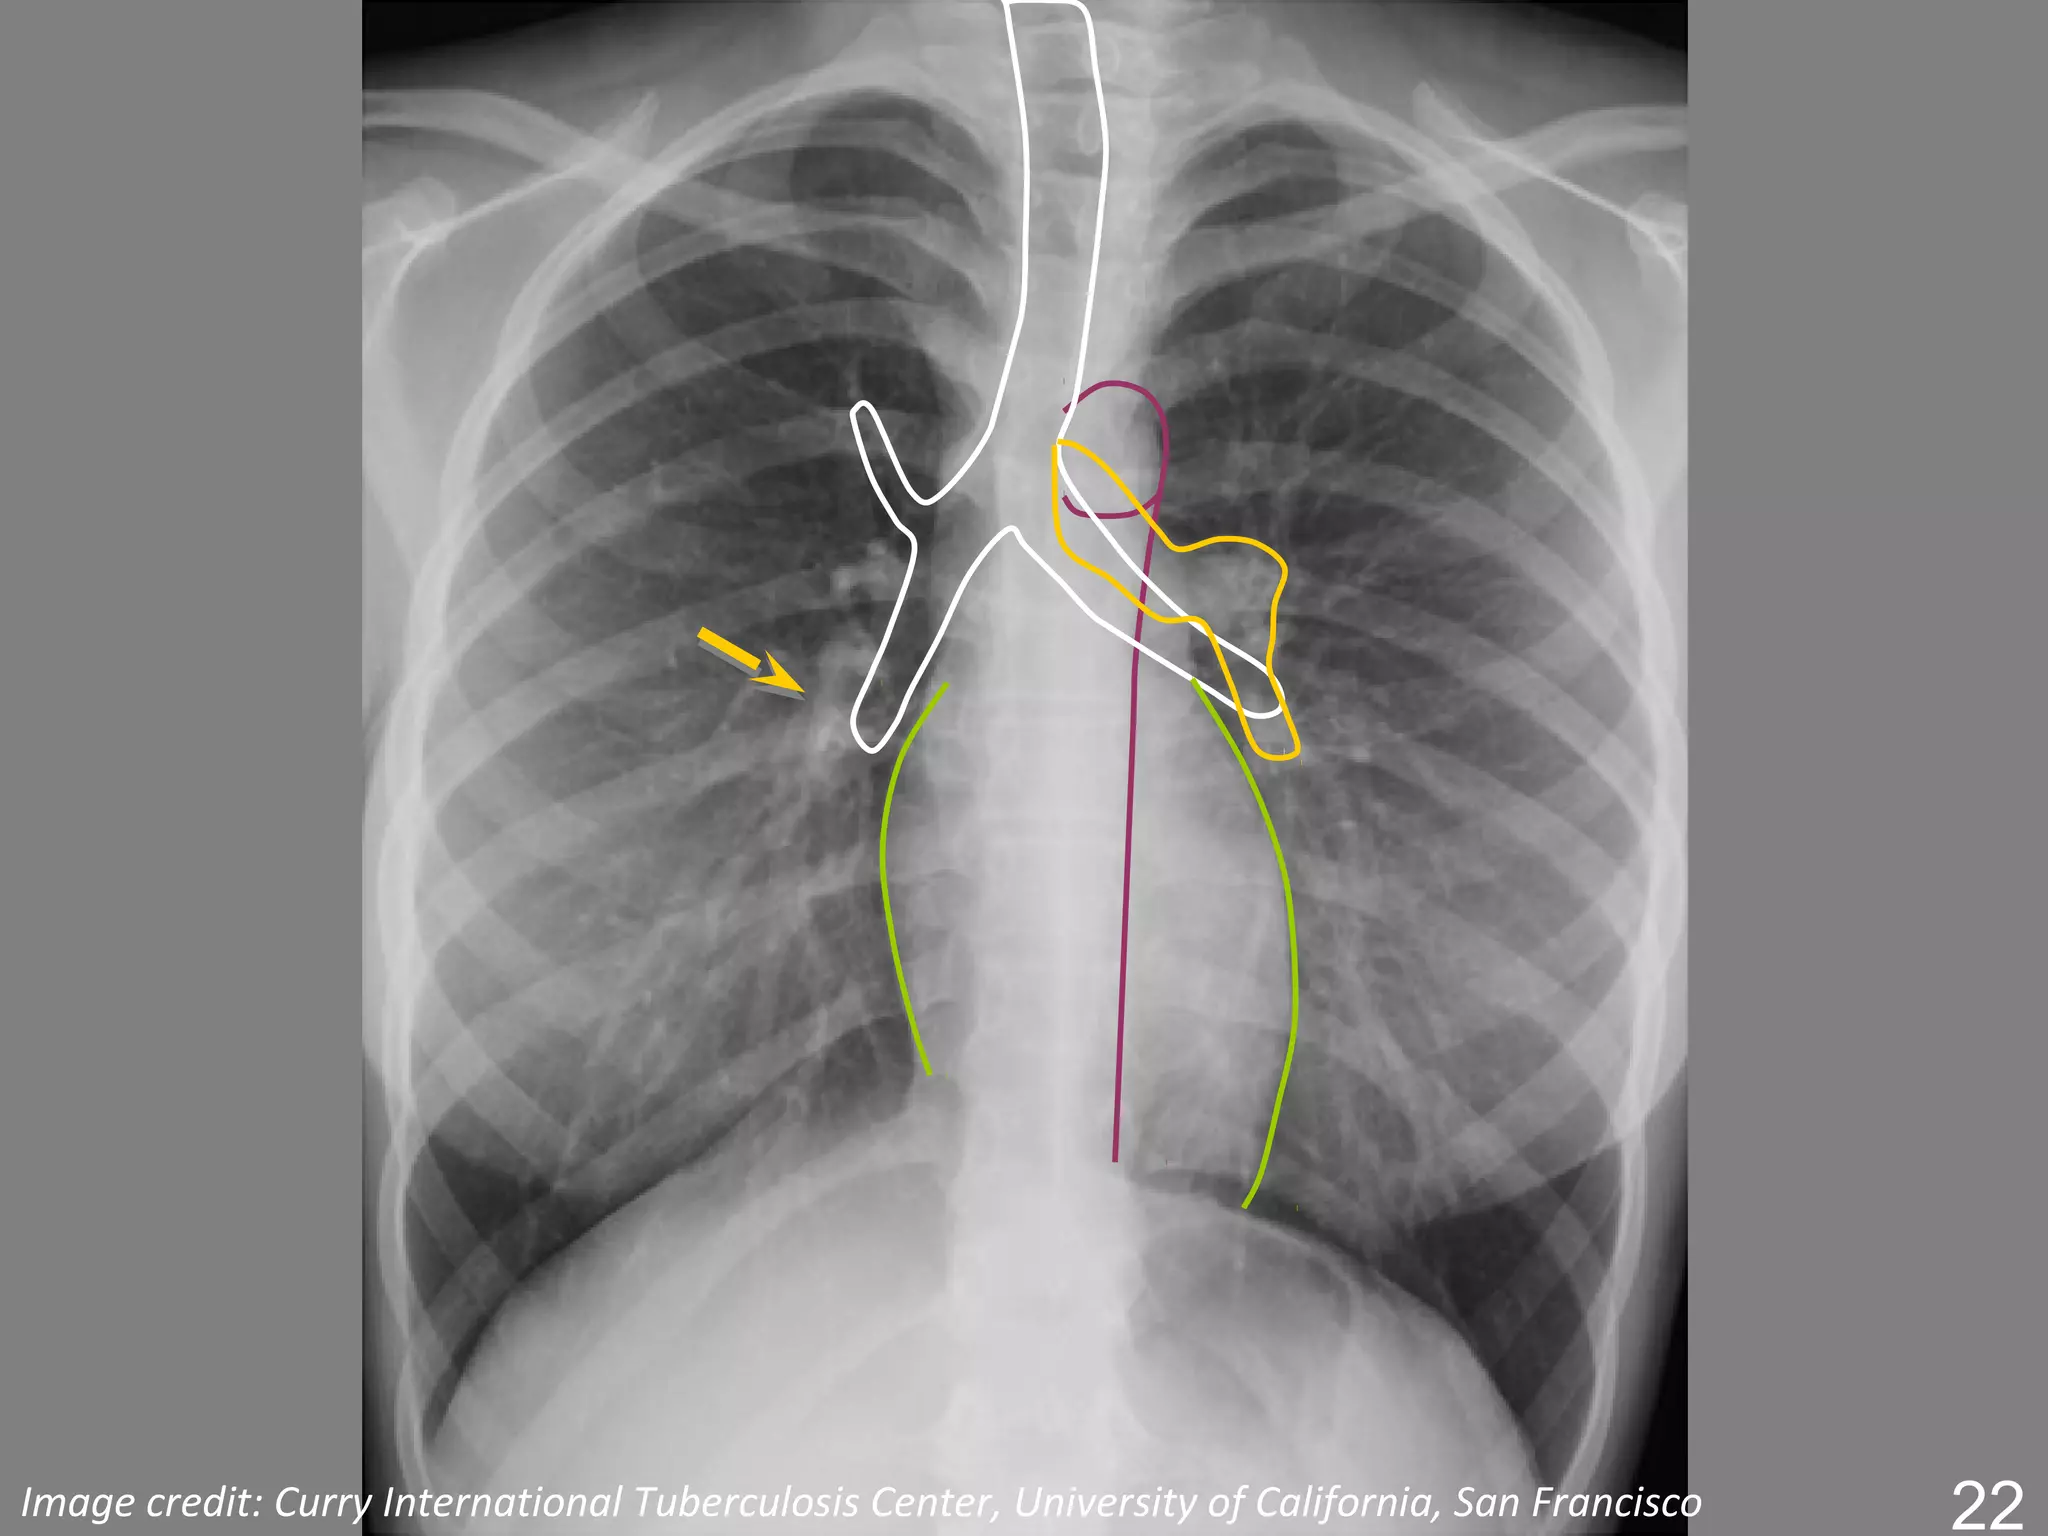

The mediastinum and heart

The central dense shadow seen on PA CXR

comprises the mediastinum, heart, spine and

sternum

The cardiac shadow lies to the left of the midline

and 1/3 to the right although it is quite variable

The transverse cardiac diameter normal for female

< 14.5 cm and for males < 15.5 cm.

The normal cardiothoracic ratio is < 50% on PA

film and < 60% in AP film.

The mediastinum andheart The central dense shadow seen on PA CXR comprises the mediastinum, heart, spine and sternum The cardiac shadow lies to the left of the midline and 1/3 to the right although it is quite variable The transverse cardiac diameter normal for female < 14.5 cm and for males < 15.5 cm. The normal cardiothoracic ratio is < 50% on PA film and < 60% in AP film. An increase in excess of 1.5 cm in the transverse diameter on comparable serial films is significant.

Superior Vessels Vena Cava Aortic Arch Ascending Aorta Pulmonary Artery Right Left Atrium Atrium Inferior Left Ventricle Vena Cava

Aortic Knob/Arch Descending Ascending Aorta Aorta Left Atrium Right Left Ventricle Ventricle Inferior Vena Cava